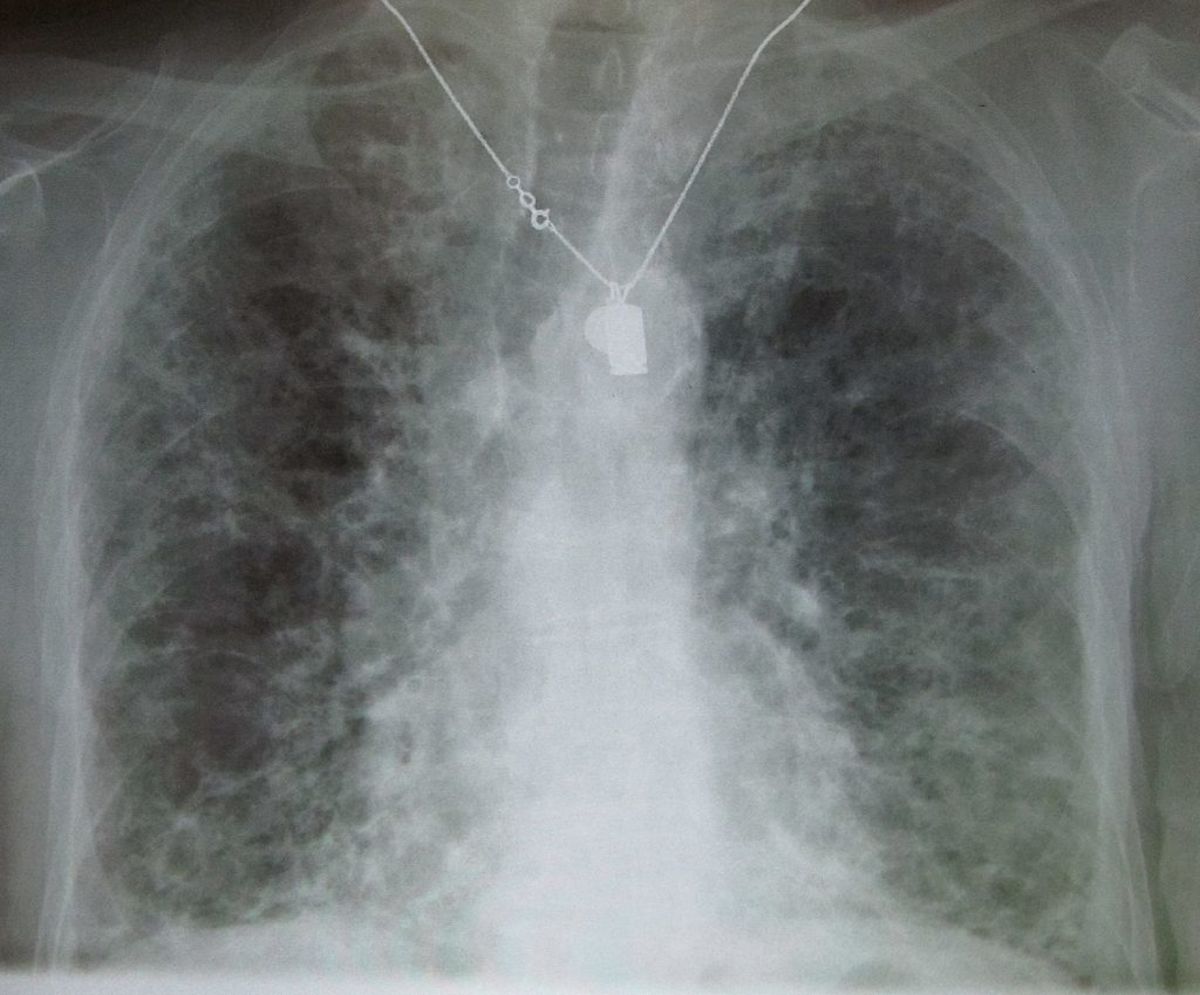

What Do Dark Spots On An X Ray Mean . If your doctor discovers a spot on your lung during an imaging study, you may worry about what it means for your health. Structures that block radiation appear white, and structures that let radiation through appear black. It is sometimes called a spot on the lung or a. (anything larger than 3 centimeters is considered as a mass.) nodules. In some cases, though, more tests might be required to ensure the. These spots are called pulmonary nodules. A nodule is defined as a lesion measuring 3 centimeters or smaller in diameter, says lung specialist louis lam, md.

If your doctor discovers a spot on your lung during an imaging study, you may worry about what it means for your health. In some cases, though, more tests might be required to ensure the. (anything larger than 3 centimeters is considered as a mass.) nodules. It is sometimes called a spot on the lung or a. These spots are called pulmonary nodules. Structures that block radiation appear white, and structures that let radiation through appear black. A nodule is defined as a lesion measuring 3 centimeters or smaller in diameter, says lung specialist louis lam, md.